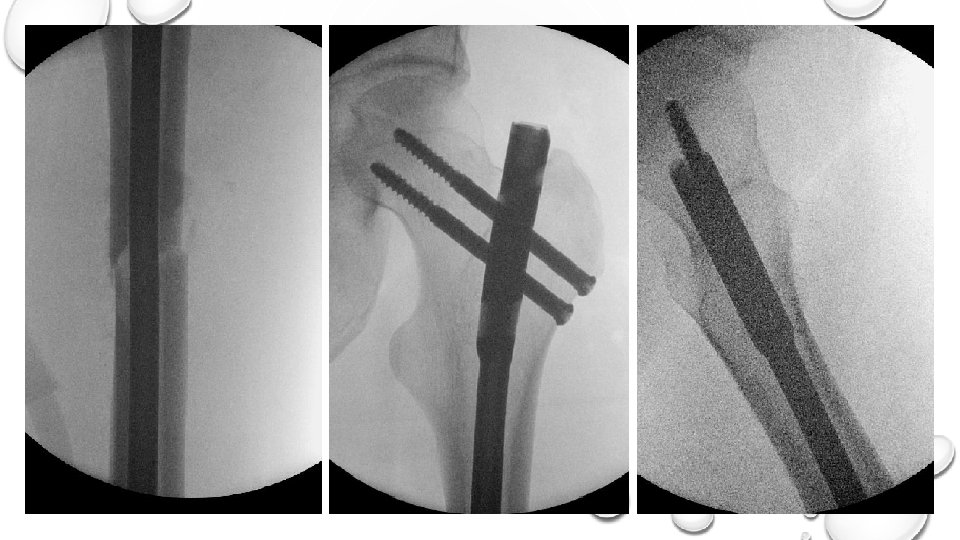

CASE 2: EARLY APPROPRIATE CARE SKELETAL PHYSIOLOGICAL ASSISTANCE • SKELETAL PHYSIOLOGICAL ASSISTANCE

Minimally invasive techniques KEY MESSAG E CASE 2 Beware the multiple long bone patient

Minimally invasive techniques KEY MESSAG E CASE 2 Beware the multiple long bone patient Regular reassessment through the case Keep the surgical hit to a minimum